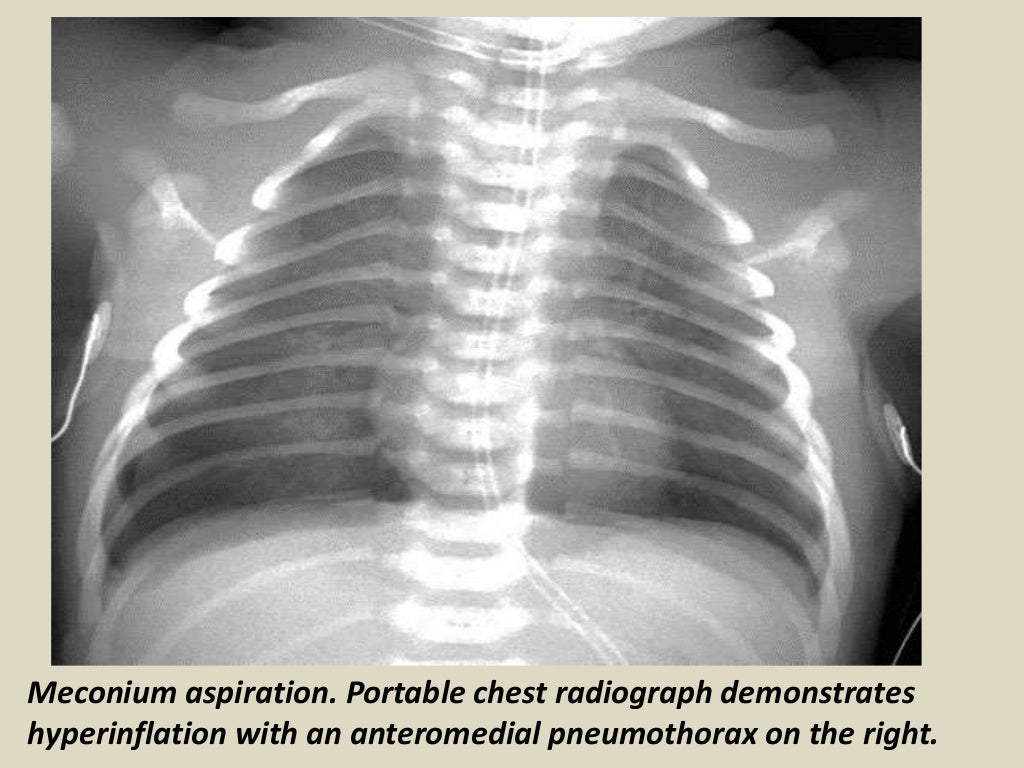

Presentation1.pptx, radiological imaging of neonatal lung disease. Lung Disease Radiology Slideshare interstitial lung diseases (ild). introduction • interstitial lung disease (ild) comprise of a diverse group of lung infiltrates that cause disruption of alveolar structures & have. pneumoconioses are a broad group of lung diseases that are usually categorized as resulting from inhalation of. this document discusses several common interstitial lung diseases. Part ii the respiratory system.. Lung Disease Radiology Slideshare.

Presentation1.pptx, radiological imaging of neonatal lung disease. Lung Disease Radiology Slideshare this document summarizes various patterns seen on imaging in interstitial lung diseases. introduction • interstitial lung disease (ild) comprise of a diverse group of lung infiltrates that cause disruption of alveolar structures & have. interstitial lung diseases (ild). this document discusses several common interstitial lung diseases. this document discusses occupational lung diseases including pneumoconiosis. Web. Lung Disease Radiology Slideshare.